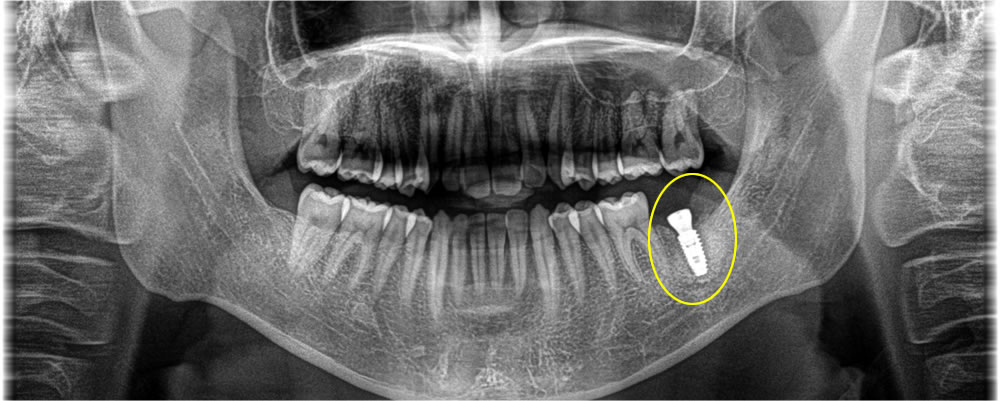

骨が無くなってしまっている部分が下歯槽神経までいってしまっていたため、まずは抜歯と同時に骨を作る処置のみを行い、5ヵ月して骨ができているのを確認した後にインプラントを埋入を行いました。

上部構造の装着・治療完了